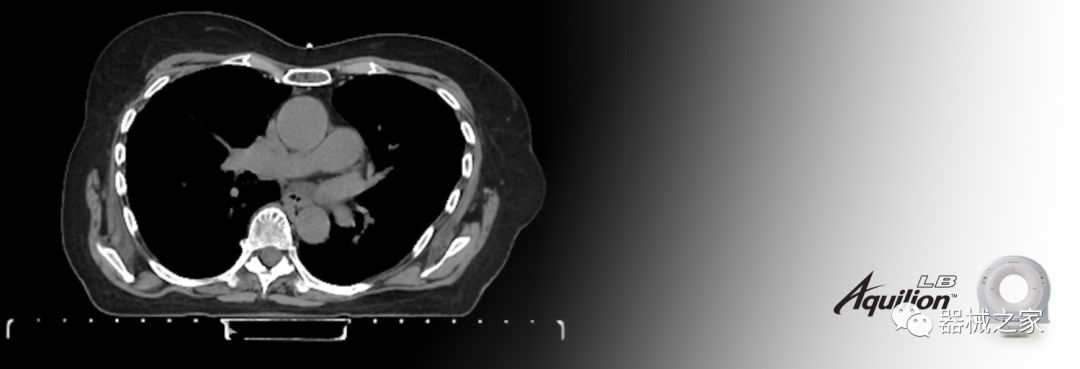

在以患者為中心的放射腫瘤學(xué)領(lǐng)域,計(jì)算機(jī)斷層掃描(CT)的可訪問性,可重復(fù)性和靈活性至關(guān)重要。為了建立這些價(jià)值,佳能醫(yī)療系統(tǒng)美國公司現(xiàn)在正在擴(kuò)大其放射腫瘤學(xué)CT模擬產(chǎn)品,包括Aquilion Prime SP和Aquilion Lightning 80高級(jí)CT系統(tǒng)。除了Aquilion LB之外,Aquilion Prime SP和Aquilion Lightning 80現(xiàn)在還包括放射治療(RT)選項(xiàng),可為腫瘤學(xué)規(guī)劃提供高質(zhì)量的CT成像和精密工具。

擴(kuò)展視野(EFOV)可以看到更多的解剖結(jié)構(gòu)。Aquilion LB采用85 cm EFOV,而Aquilion Prime SP和Aquilion Lightning 70采用70 cm EFOV。

Aquilion LB專為滿足腫瘤學(xué)挑戰(zhàn)而設(shè)計(jì),同時(shí)優(yōu)先考慮患者護(hù)理。Aquilion LB的內(nèi)徑為90 cm,能夠幫助復(fù)雜的患者設(shè)置并提高患者的舒適度。CT模擬定位可以輕松鏡像放射治療定位,更加自信。該系統(tǒng)采用0.5 mm x 16排(32層)PUREViSION探測(cè)器技術(shù),70 cm視野,AIDR 3D和SEMAR技術(shù)。